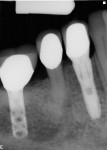

All 29 immediately placed and temporized implants in this study achieved osseointegration and received definitive restorations, resulting in 100% survival. None displayed bone loss greater than 1 mm radiographically at a minimal loading time of 12 months. No continuous radiolucencies were noted, and none of the sites required surgical revision or loss of the restorations. All patients verbally expressed satisfaction with the esthetic outcome, and all cases were considered successful. Of the 29 fixtures, 25 showed proximal bone radiographically at or above the head of the implant, with a cumulative BM of 86%. Examples of BM are depicted in Figure 22 through Figure 26.